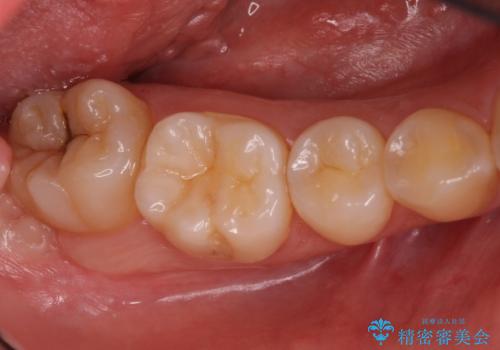

奥歯の深い黒ずみ セラミックインレーでの治療

- 奥歯の溝の黒ずみが気になるとのことで来院されました。

変色しない材料をご希望されたためセラミックインレーでの治療となりました。

- 右下7 セラミックインレー 77,000円費用は治療当時の料金となります